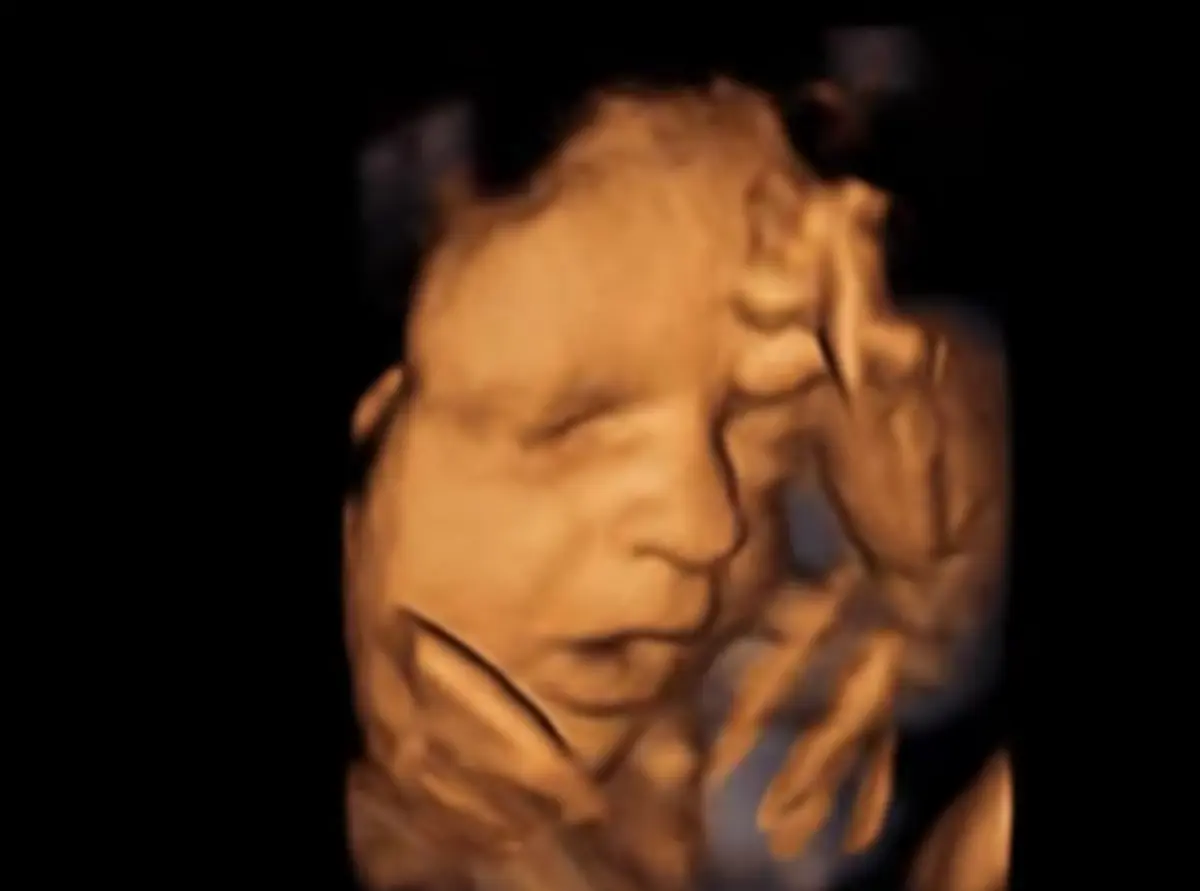

A Entidade Reguladora da Saúde (ERS) alertou, esta terça-feira, para os riscos das "ecografias emocionais", sublinhando que estes exames só devem ser realizados em "contexto clínico" e não podem ser prestados com fins recreativos, como a "mera visualização" do feto.

O aviso do regulador da saúde surge na sequência de várias reclamações de utentes a relatarem a "realização de ecografias designadas como 'emocionais', '3D/4D/5D não diagnósticas' ou equivalentes, que se apresentam como serviços de caráter recreativo, com o propósito de proporcionar às grávidas e respetivas famílias uma experiência visual e sentimental".

De acordo com a ERS, estas práticas "podem implicar a exposição desnecessária do feto a ultrassons e desvirtuam a finalidade médica e diagnóstica da ecografia obstétrica, contrariando as recomendações técnico-científicas vigentes".